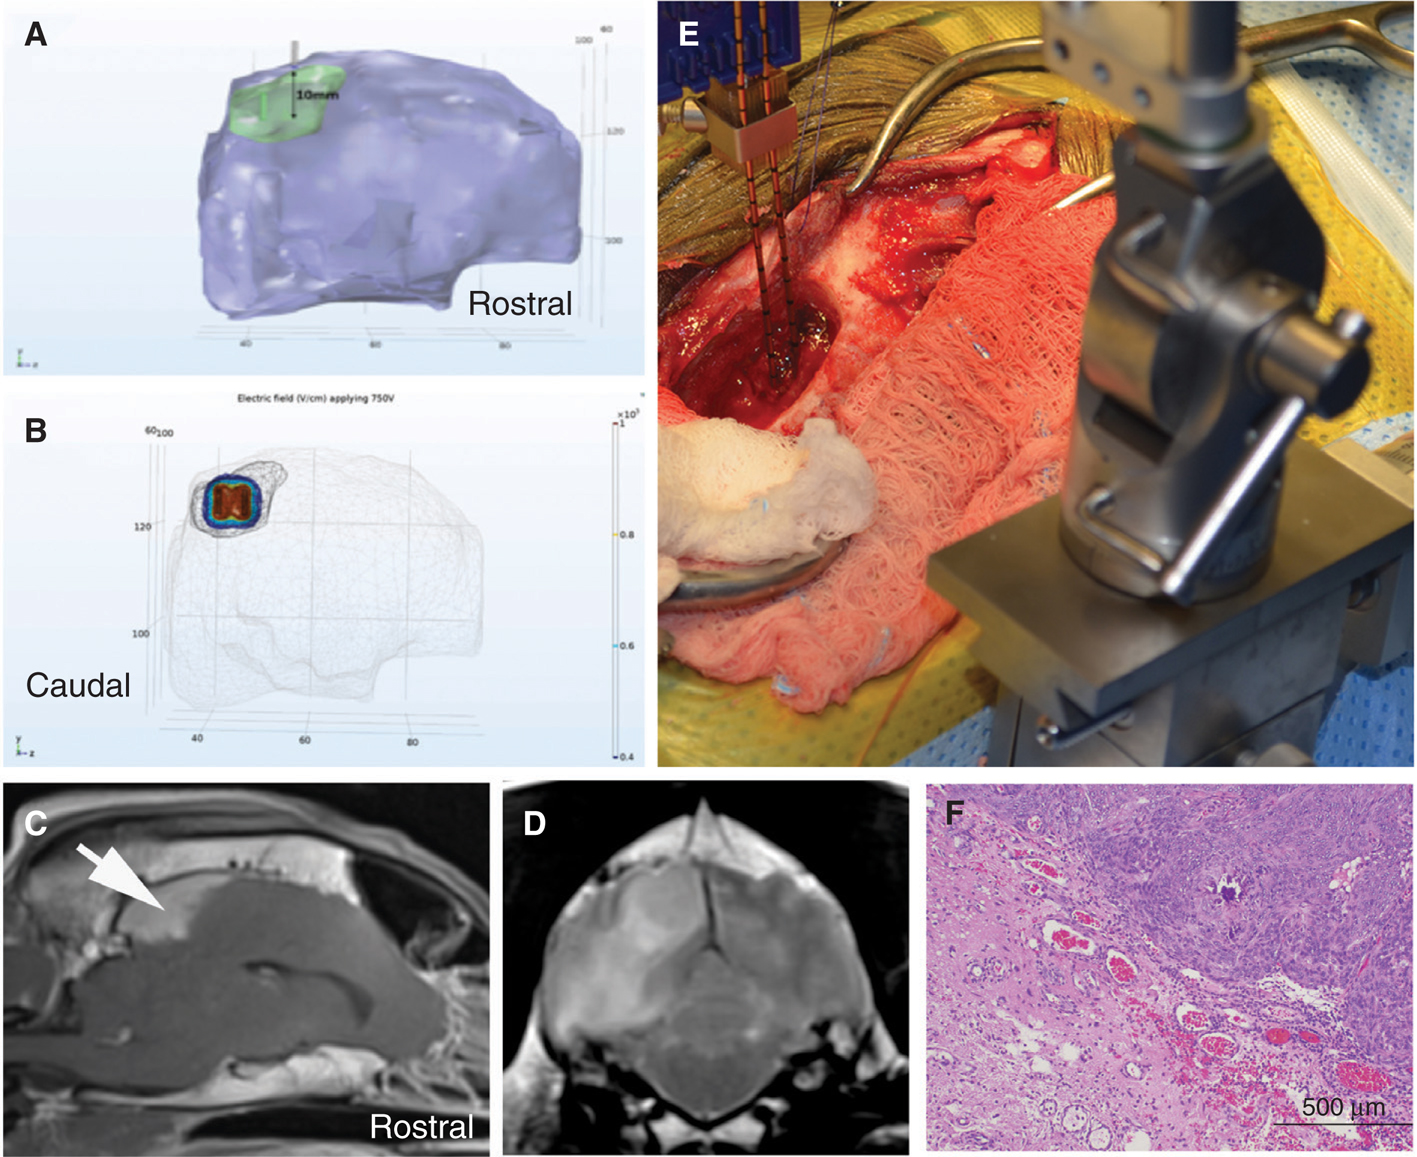

We have evaluated the safety and preliminary efficacy both IRE (Figure 3) and H-FIRE (Figure 4) in dogs with spontaneous brain tumors (77, 79, 86). An integral component of the preclinical evaluation of IRE and H-FIRE was the development of anatomically accurate numerical treatment planning models that maximize tumor coverage while minimizing damage to surrounding healthy tissue and also account for the increase in tissue conductivity that occurs during pulse delivery (86–88). Incorporating therapeutic plans developed from patient-specific, segmented medical images imported into finite element analysis modeling software, we have confirmed the ability of IRE and H-FIRE to safely and precisely ablate normal and neoplastic canine brain tissues with a submillimeter line of demarcation between ablated and non-treated tissues (79, 86, 89). IRE treatment of canine gliomas resulted in significant objective tumor responses in 4/5 dogs with quantifiable target lesions (Figure 3), and these radiographic responses were accompanied by improvements in Karnofsky performance scores and posttreatment seizure control (72, 86). Similarly, using a treat and resect treatment paradigm, we have confirmed the ability of H-FIRE to safely and precisely ablate clinically relevant volumes of canine brain tumors without the induction of muscular contractions during pulse delivery (Figure 4).

Figure 3 Stereotactic glioblastoma ablation with irreversible electroporation (IRE). Pretreatment transverse (A) and dorsal planar (B) post-contrast T1-weighted MR demonstrating ring-enhancing glioblastoma in the frontoparietal lobe of the cerebrum. Co-registered intraoperative CT and pre-treatment MR images (C) and three-dimensional reconstructed CT (F) with IRE electrodes in situ within the tumor in preparation for ablation. Three-month post-IRE treatment transverse (D) and dorsal planar (E) post-contrast T1-weighted MR illustrating 95% reduction in tumor burden.

Figure 4 High-frequency irreversible electroporation (H-FIRE) treatment of a canine Type I parasagittal meningioma. Treatment planning (A, B) involves segmentation of the tumor (green) and brain (purple) from the patient’s MR images (C, D), and determination of the electrode placement trajectory (A). The resulting electric field distributions are then simulated (B) using finite element analysis software (B). The H-FIRE electrodes are placed using intraoperative stereotaxy (E) according to the treatment plan, and the pulses delivered. After-HFIRE treatment, the tumor was resected and serially sectioned to correlate the predicted with actual ablation volume. Photomicrograph of the treatment margin (F), illustrating a sharp line of demarcation between H-FIRE ablated (lower left) and viable tumor (upper right); H&E stain.

To overcome previously recognized barriers to the translation IRE and H-FIRE therapies to the clinic, such as the inability to incorporate MR image-guidance into treatments and need to use multiple software programs for therapeutic planning, we have been developing a comprehensive solution that combines all of the necessary components of the workflow in a user-friendly platform that can be incorporated into contemporary neurosurgical theaters (86, 90, 91). The foundation for this platform is an open-source, online interface that uses a treatment planning approach similar to that employed in radiotherapeutic applications. The software allows for tissue-specific segmentation, determination of the tumor dimensions, and formulation of virtual electrode insertion approaches that can be used in surgery (91). These volumetric representations are then used to perform computational simulations of the electric field distribution surrounding the active electrodes during pulse delivery to determine tumor coverage (Figure 4) and cell kill probabilities (90, 92). Validation of the predicted therapeutic outcomes generated with this platform is currently underway using clinical data from IRE-treated dogs with intracranial gliomas (90).